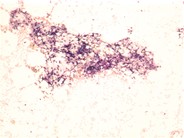

Hypocellular Bone Marrow Following Therapy - 2.

A high power view reveals the relative absence of hematopoietic cells. Instead, debris laden histiocytes and stromal elements are noted.